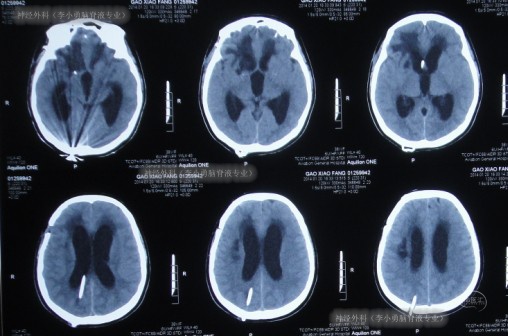

2013年11月11日即术后7天时,患者中度昏迷,伴有呼吸困难,立即进行头颅CT检查发现了脑严重肿胀的表现(图-4)。

图-4:术后7天头颅CT

2013年11月18日即术后第14天(腰大池外引流管拔除后第6天),神志转清,右手能写字,但存在吞咽障碍、发音障碍、左侧肢体无力表现,复查头颅CT(图-5)示水肿减轻,脑室稍扩张。考虑患者处于恢复期,脑室可逐渐恢复正常,并将其转入普通病房继续治疗。

图-5:术后14天头颅CT

继续治疗14天内,患者逐渐出现表情呆滞,反应迟钝,昏睡,在2013年12月2日即动脉瘤夹闭术后28天,复查头颅CT示脑室扩张加重及脑室周围水肿明显(图-6)。

图-6:术后28天头颅CT